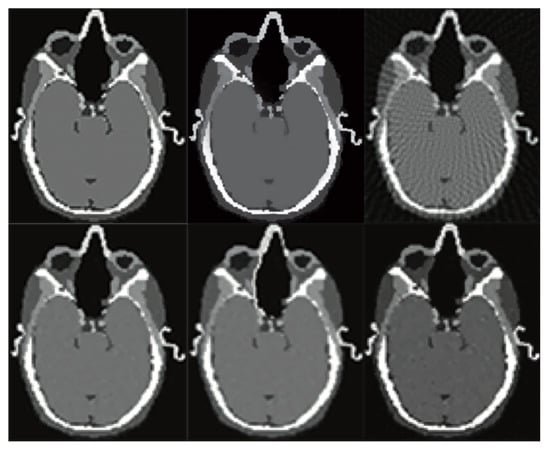

3. Computed Tomography Imaging Speeding Up

4. Compressively Sensed CT/PET Signals

6. Evaluation

7. Results